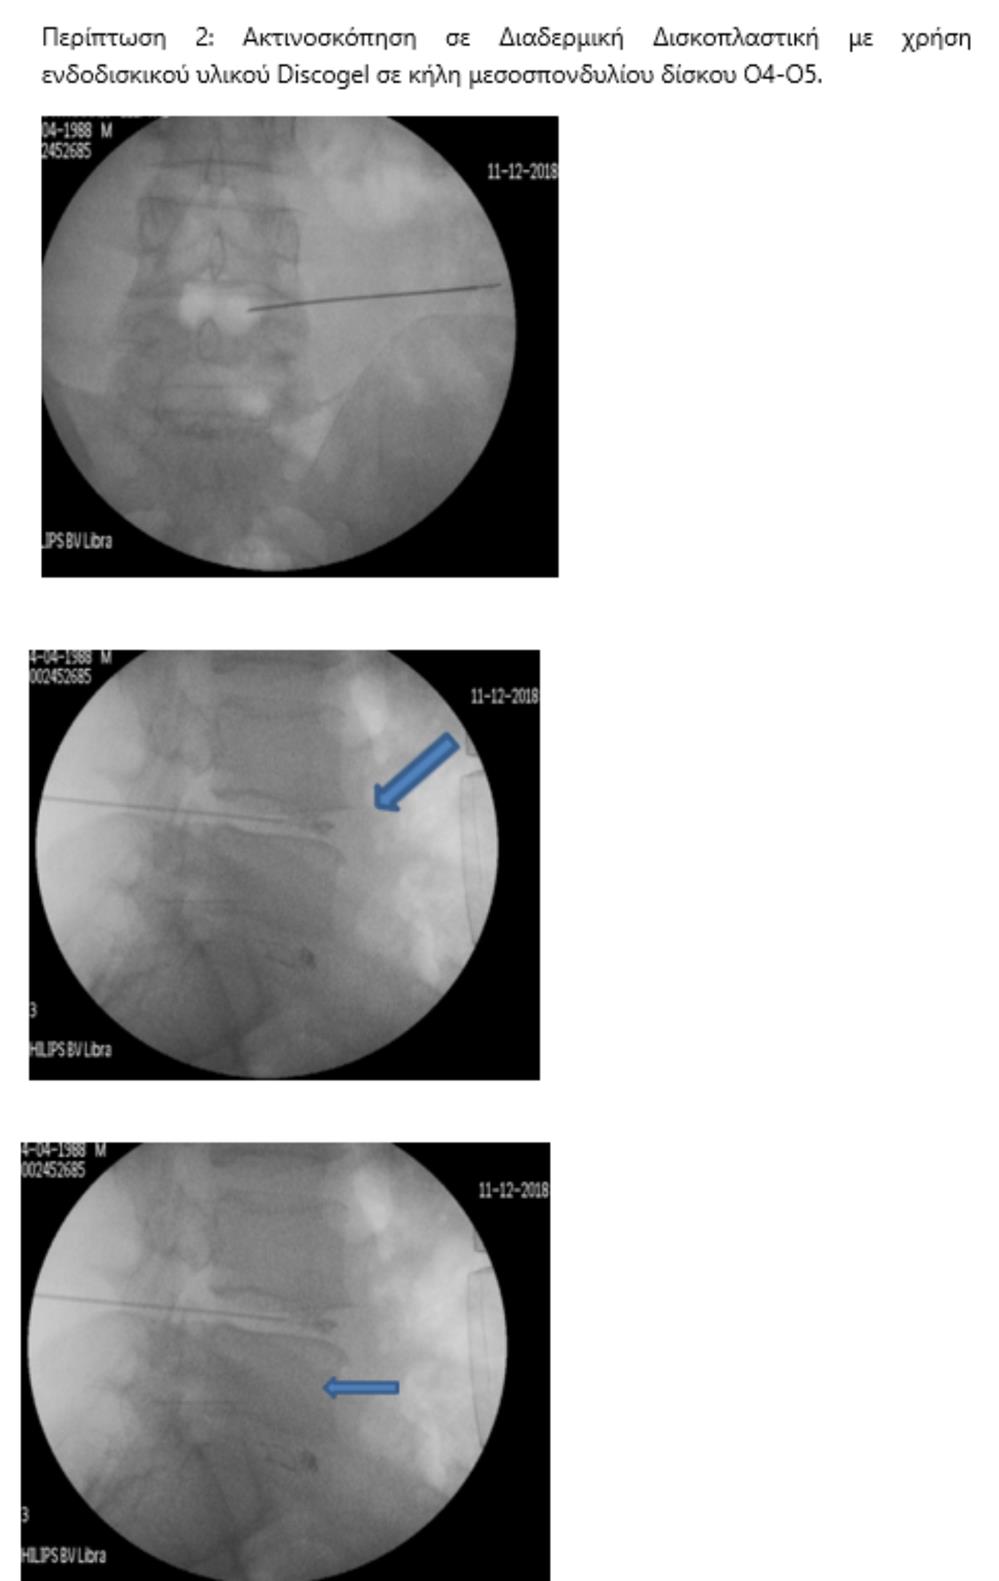

Με τον δεύτερο τρόπο γίνεται, υπό ακτινοσκοπικό έλεγχο, διαδερμική έγχυση ενός υλικού που έχει μορφή γέλης (gel) και συνίσταται από αιθανόλη, παράγωγα κυτταρίνης και ακτινοσκιερό υλικό tungsten  (σχ.3). Η έγχυση γίνεται στο κέντρο του δίσκου, μέσα από έναν οδηγό και λειτουργεί άμεσα. Η δράση του διαλύματος στηρίζεται στις φυσικοχημικές ιδιότητές του: απορροφητική επίδραση της αιθανόλης με το νερό, που περιέχεται στον δίσκο, σε συνδυασμό με ένα φαινόμενο ώσμωσης- αφυδάτωσης του δίσκου από την περιφέρειά του προς τον πυρήνα του. Έτσι, «απορροφάται» η προβολή του δίσκου πίσω προς το κέντρο του (σχ.4).